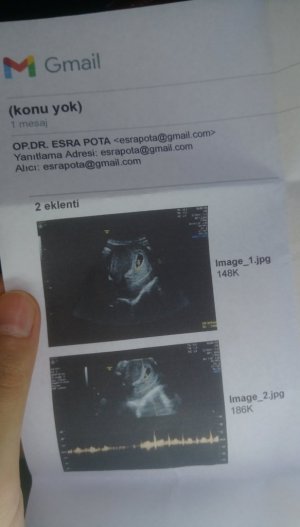

Ultrason dan cinsiyet tahmini

100 de 100 erkek diyebilirim nubu dik saglicakla alirsin kucaginaArkadaşlar merhaba daha önce burada ultrason fotoğrafına bakıp cinsiyet tahmin edenleri görmüştüm benim içinde bi heyecan olur:) var mıdır tahmininiz normalde 12+4 üm ama ultrasonda 13 haftalık görünüyor

Merhabalar 11 haftalık ultrason görüntüsü için cinsiyet tahmini yapabilir misiniz ?Arkadaşlar merhaba daha önce burada ultrason fotoğrafına bakıp cinsiyet tahmin edenleri görmüştüm benim içinde bi heyecan olur:) var mıdır tahmininiz normalde 12+4 üm ama ultrasonda 13 haftalık görünüyor

Bnim ultrason resmine çok benziyor bence kesin erkekArkadaşlar merhaba daha önce burada ultrason fotoğrafına bakıp cinsiyet tahmin edenleri görmüştüm benim içinde bi heyecan olur:) var mıdır tahmininiz normalde 12+4 üm ama ultrasonda 13 haftalık görünüyor

Bnim ultrason resmine çok benziyor bence kesin erkek

7-8 haftaşık ultrason resmi varsa iyi tahmin yaparımArkadaşlar merhaba daha önce burada ultrason fotoğrafına bakıp cinsiyet tahmin edenleri görmüştüm benim içinde bi heyecan olur:) var mıdır tahmininiz normalde 12+4 üm ama ultrasonda 13 haftalık görünüyor

Kaç haftalıkMerhabalar 11 haftalık ultrason görüntüsü için cinsiyet tahmini yapabilir misiniz ?

7-8 haftalık görüntü varsa at canımMerhabalar 11 haftalık ultrason görüntüsü için cinsiyet tahmini yapabilir misiniz ?

Erkek gıbıArkadaşlar merhaba daha önce burada ultrason fotoğrafına bakıp cinsiyet tahmin edenleri görmüştüm benim içinde bi heyecan olur:) var mıdır tahmininiz normalde 12+4 üm ama ultrasonda 13 haftalık görünüyor